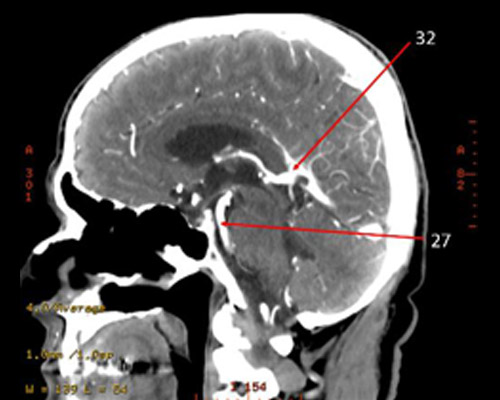

27?

27 = basilar

32?

32 = posterior CA